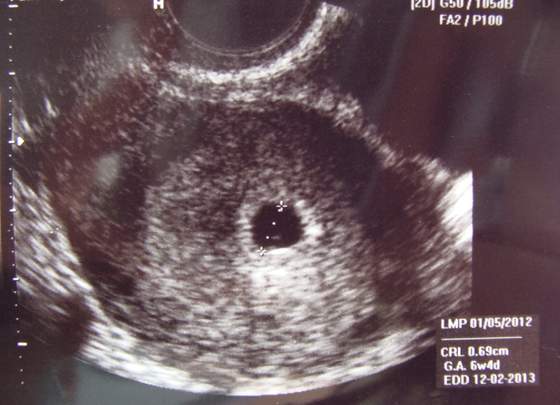

Wygrzebałam moje zdjęcie z tego USG na którym "nic"nie ma. Teraz młody ma około 2140g :-D

Zobacz załącznik 528196

Hej dziewczyny też mam problem w poniedziałek miałam u ginekologa diagnozę pustego jaja płodowego z miesiaczki wychodzi mi 10 tc byłam na NFZ nie widział wgl zarodka i wyszło mu że jestem w 7 tyg i 6 dniu wczraj poszłam prywatnie i ginekolog nie jest pewien ale coś na zdjęciu USG wyszło i stwierdził że jestem albo 5tyg i 5 dzień / 6tydz i 1dzien CRL ma 0.23 i nie jest pewien dał na HCG beta dwa razy niewiem co myśleć.